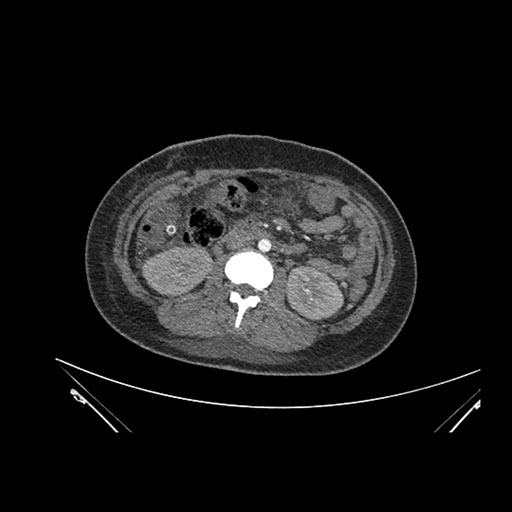

Coronal Venous

Imaging analysis

Based on initial findings, which issue(s) would you be most concerned about?